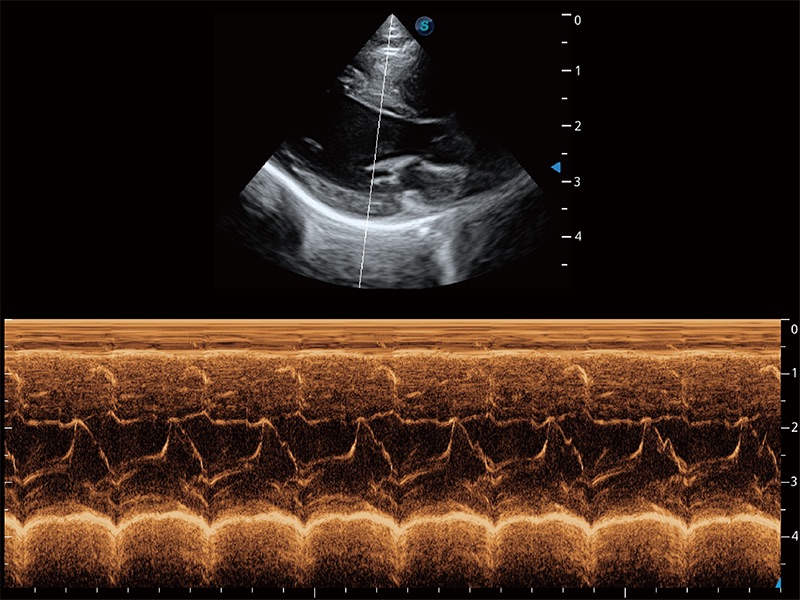

• AMM 解剖M型

通过360度任意调节3条M型取样线,在同一心动周期上观察心脏不同位置的运动曲线,得到准确的心功能测量数据,有效评估心肌运动及左心室功能。

(猫)二尖瓣M型

(犬)二腔心血流

得心应手 心脏解决方案

ProPet 80 配备了丰富的心脏探头群、先进的成像技术和专业的心脏测量工具,可帮助动物医生为不同体型和生理结构的动物提供心脏和心肌功能的全面评估。